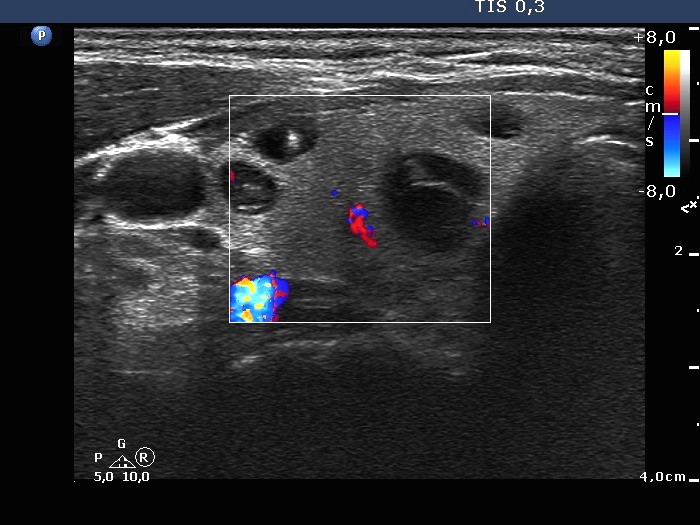

Right lobe, transverse scan, color Doppler mode. The vascularization is not specific.